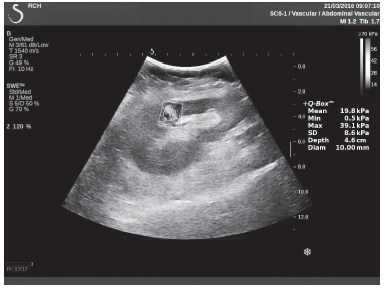

Клинический пример из первой группы. Пациент М., с хронической почечной недостаточностью. Трансплантация почки произведена от живого родственного донора. Трансплантат находится в правой подвздошной области. При нормальном функциональном состоянии трансплантата, показатели цветовой и спектральной допплерографии оценивались как удовлетворительные, с индексом резистентности не более 0,60 (рис. 1); показатели жесткости паренхимы почечного трансплантата при УЭСВ на различных участках составили от 20,05 до 29,18 кПа (рис. 2-4).

Рисунок 2. Исследование в режиме ультразвуковой эластографии сдвиговой волны у пациента М.: жесткость паренхимы в зоне медиального края трансплантата 19,8 кПа